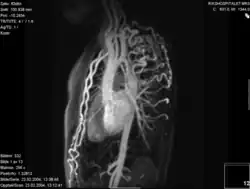

- Die Magnetresonanztomografie (=Kernspintomografie, MRT, NMR) ermöglicht eine gute Darstellung der ISTA. Durch die Flussmessungen ist eine Gradientenabschätzung möglich und gleichfalls eine 3-D-Rekonstruktion durchführbar.

Aortenisthmusstenose – Rekonstruktion 3D

Aortenisthmusstenose – Rekonstruktion 3D -